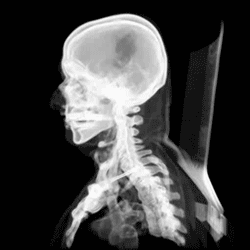

Identification of Axial Bones